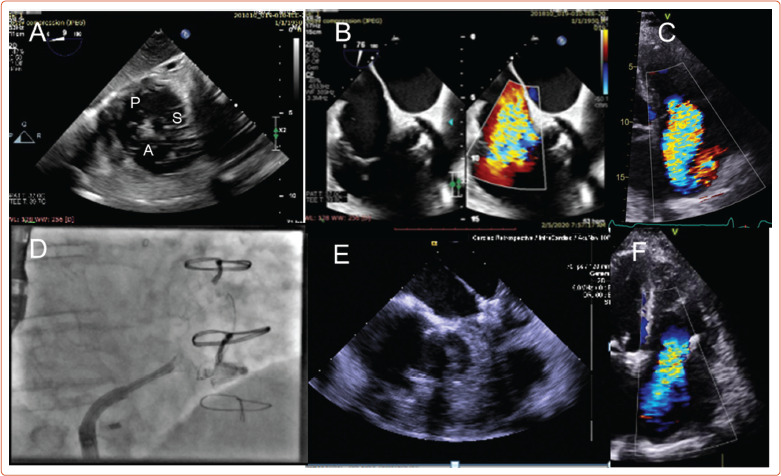

Abstract Image